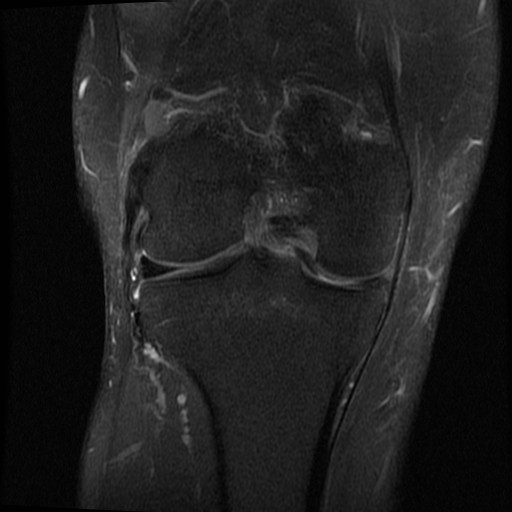

Mann i 30 årene. Vridningstraume 4 måneder siden; “ikke blitt bra ennå”, ønsket MR kne.

Diagnose: Bøttehank ruptur av fremre del av mediale menisk, såklat “double ACL sign”.

Sees også tydelig på coronale og axiale bilder (bilde 2 og 3):

Referanse: The double ACL sign: an unusual bucket-handle tear of medial meniscus

Koji Takayama, Takehiko Matsushita, Tomoyuki Matsumoto, Seiji Kubo, Masahiro Kurosaka, Ryosuke Kuroda

Knee Surgery, Sports Traumatology, Arthroscopy; August 2011, Volume 19, Issue 8, pp 1343-1346